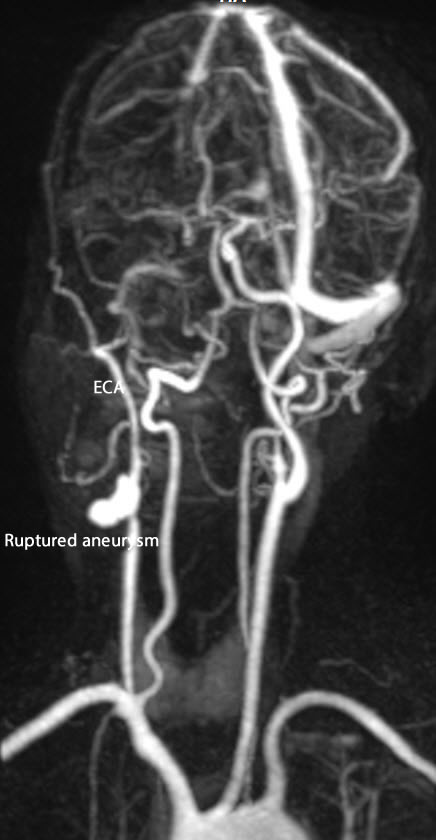

The patient then came 01-May-2019 with oozing of the mass after manipulation by a doctor. The patient was advised to keep in conservative treatment. The patient then came 03-November-2019 telling that yesterday, he progressed loss of vision right eye for 30 minutes then recovered. He has small clot at the most upper anterior edge of the previous incision. He told me that all the period the wound was quite, and subcutaneous mass appeared at the center of the incision. It was pulsating, for what another MRI investigation was performed and MRA of the right carotid was showing an aneurysm at the bifurcation of the CCA. The patient was advised to stop plavix and baby aspirin and try conservative treatment. The patient then came to the emergency of Shmaisani hospital, transferred from other hospital after resuscitating him from massive bleeding with hypovolimic shock. When I saw him, he was alert and the bleeding was stopped and advised to have blood transfusion with FFP to prepare him to surgery. Before transfusion the Hb was 10.7 mg/dL.

Fig-2: The ruptured aneurysm with external bleeding caused hypovolimic shock with absent right ICA and preserved ECA.